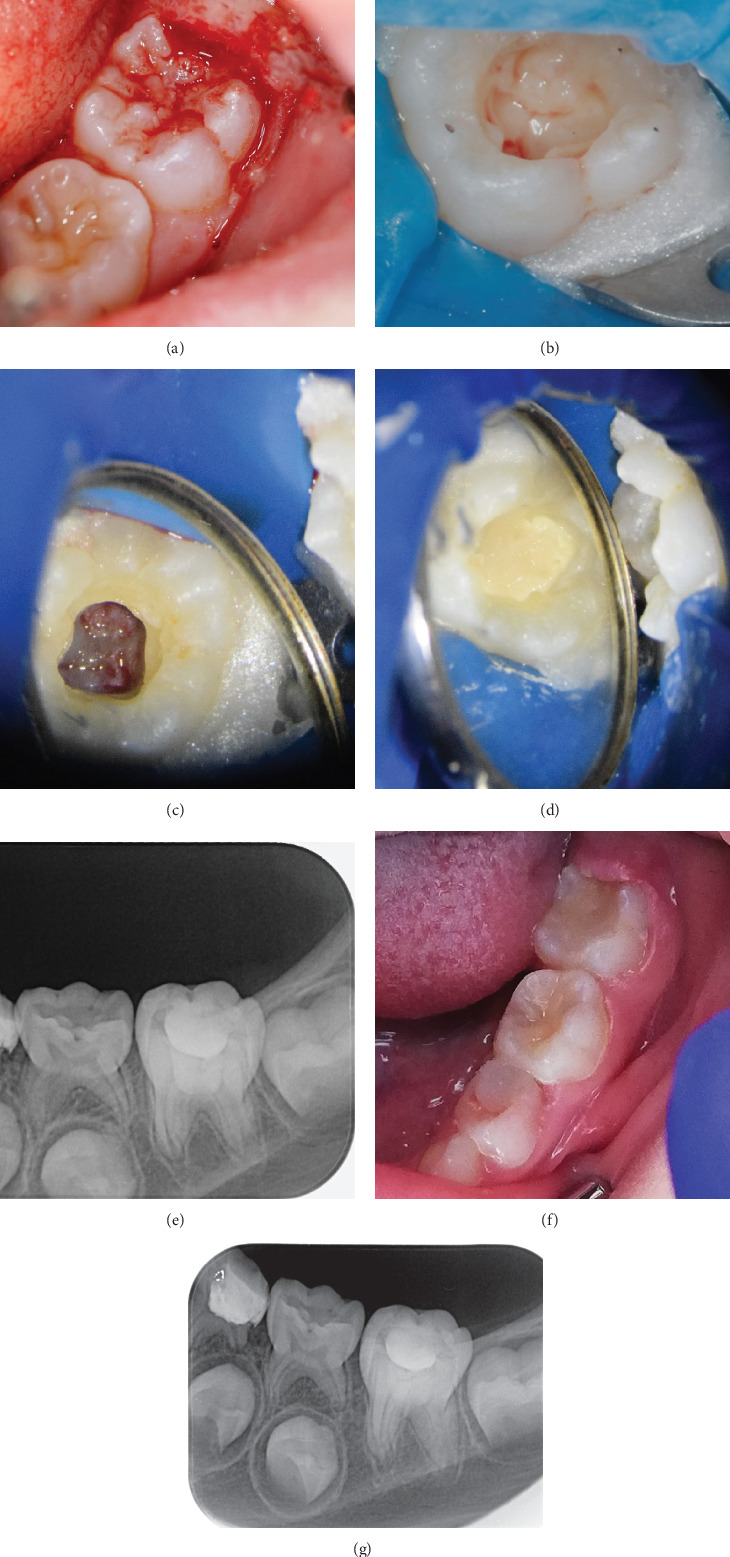

Intracoronal resorption (IR) is a condition characterized by the presence of lesions in the dentin of unerupted or erupting teeth, usually located just below the enamel-dentin junction in the occlusal part of the crown. This article presents two cases of IR-one with and one without pulp involvement. In both cases, the teeth were asymptomatic, and the lesions were discovered during routine checkups. The first case presents pre-eruptive IR with pulp involvement in an immature mandibular molar. To preserve the vitality of the growth zone and complete root development, vital pulp therapy was performed through total coronal pulpotomy and application of Biodentine. The second case is also of a mandibular molar with incomplete root development, but although it initially resembled invasive cervical resorption, treatment revealed that the granulation tissue was surrounded by intact enamel and did not affect the pulp or root of the tooth. No carious lesion was found. The tooth was conventionally restored with a composite filling.